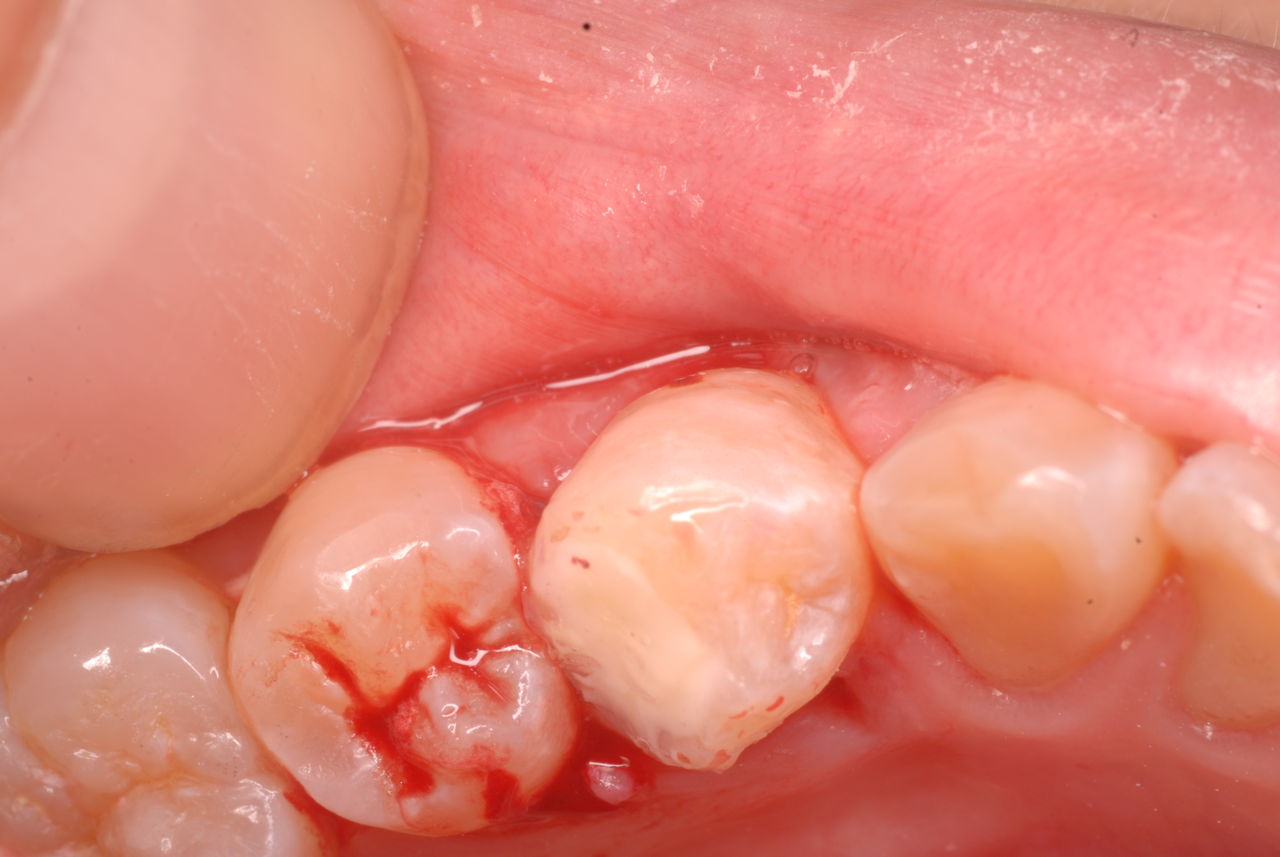

ある患者さんが紹介で急遽来院しました。

歯が痛くていつも通っている歯科で見てもらったところ虫歯が酷く、

神経を抜かなくてはならないと言われ、友達に相談。その患者さんはたまに問題があるときに来院するかたで彼女からの紹介だったのです。

注射もせずに取れるだけ虫歯という病原菌を丁寧に除去し、消毒し、ぎりぎりのところで鎮静効果を持つセメントで被覆するのです。

まだ虫歯は残っていますが危険なので除去せずにそのまま消毒して鎮静セメントを挿入しました。

隣の歯との間をプラスチックで閉鎖し、唾液の侵入を防ぎました。でもまだ虫歯は残っています。